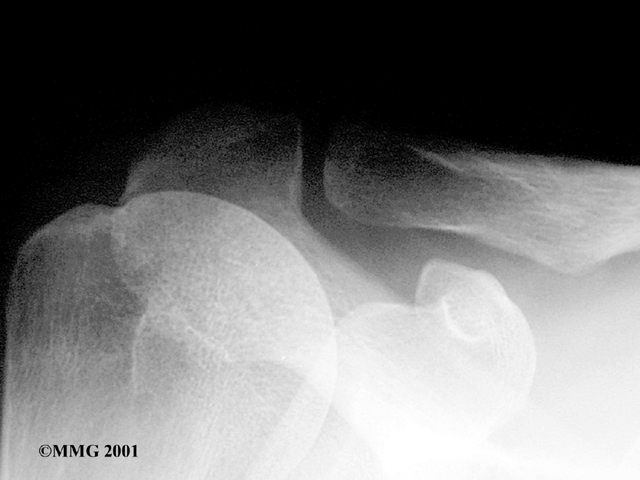

Your doctor may order an X-ray. X-rays can help confirm that your shoulder was dislocated or injured in the past.

X-Ray

When you go to the doctor with a dislocated shoulder, X-rays are necessary to rule out a fracture.

X-rays are usually done after the shoulder is put back into joint. This allows your doctor to make sure the joint is back in place.